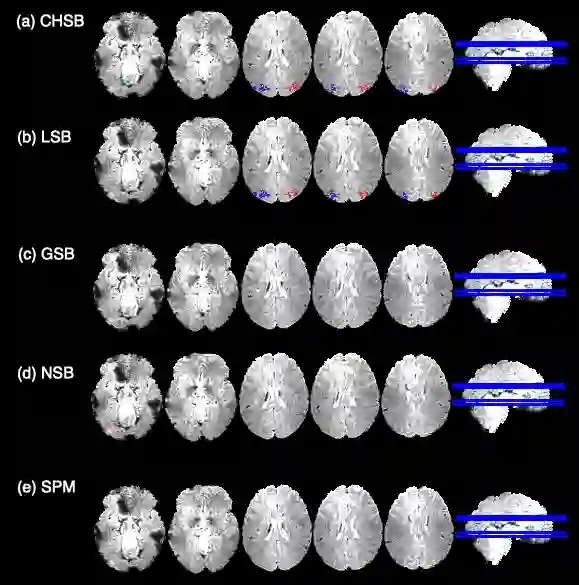

In this paper, we introduce a new Bayesian approach for analyzing task fMRI data that simultaneously detects activation signatures and background connectivity. Our modeling involves a new hybrid tensor spatial-temporal basis strategy that enables scalable computing yet captures nearby and distant intervoxel correlation and long-memory temporal correlation. The spatial basis involves a composite hybrid transform with two levels: the first accounts for within-ROI correlation, and second between-ROI distant correlation. We demonstrate in simulations how our basis space regression modeling strategy increases sensitivity for identifying activation signatures, partly driven by the induced background connectivity that itself can be summarized to reveal biological insights. This strategy leads to computationally scalable fully Bayesian inference at the voxel or ROI level that adjusts for multiple testing. We apply this model to Human Connectome Project data to reveal insights into brain activation patterns and background connectivity related to working memory tasks.